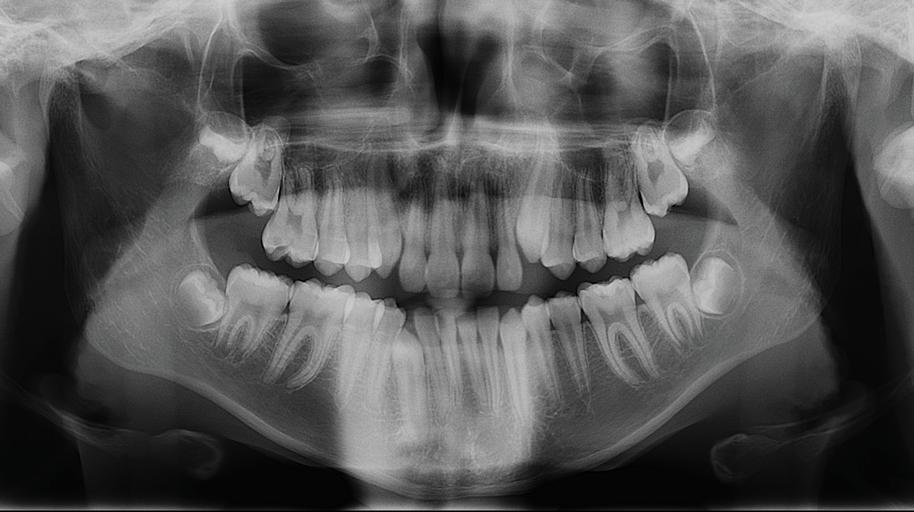

Fig 4. Initial panoramic x-ray.

Figure 4

The following case illustrates the complete surgical/orthodontic treatment sequence for an impacted maxillary right central incisor. An 8½-year-old patient presented with a chief complaint of crowded teeth. The maxillary left central incisor was the only erupted incisor at the time of consultation (Figure 2 and Figure 3). Crowding was clinically diagnosed visually by the prominence of the unerupted right central incisor in the vestibule, and this was confirmed with a panoramic radiograph (Figure 4).

The maxillary right permanent centralincisor had a delayed eruption of 1½ years compared to its homologous incisor, and it was anteriorly displaced due to insufficient space in the premaxilla. Removal of the maxillary deciduous canines was indicated to unravel the crowding. An apically positioned flap of the impacted right central incisor was made to facilitate its eruption (Figure 5 and Figure 6). The case was worked up to plan an active phase l treatment, consisting of palatal expansion and the use of sectional fixed appliances in the upper arch. A transverse deficiency without posterior crossbite was identified, and therefore palatal expansion with a bonded expander was planned to widen the premaxilla (Figure 7 and Figure 8). A two-by-four fixed appliance system (brackets in the four maxillary anterior teeth and bands on the maxillary first molars) was used to align the maxillary teeth. The gingival margin of the retained maxillary right central incisor was slightly more apical than the left one, which erupted as expected (Figure 9 and Figure 10). Figure 11 shows a panoramic radiograph taken after completion of phase 1 treatment.